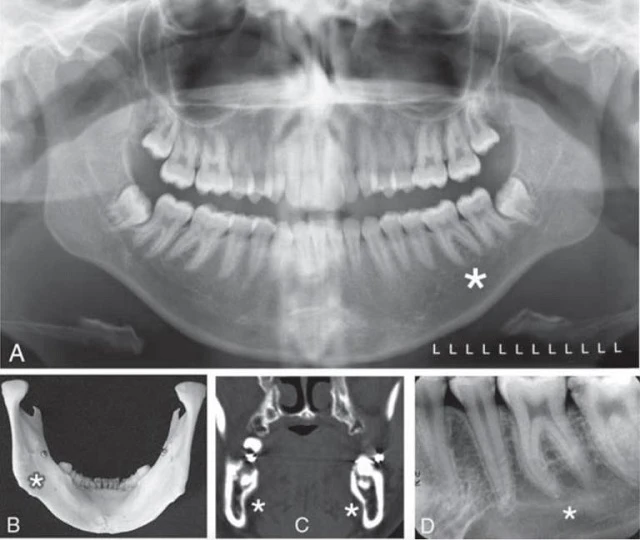

Thường có những chỗ lõm trên mặt trong của xương hàm dưới, là chỗ của các tuyến dưới hàm và dưới lưỡi: những chỗ lõm này gọi là chỗ lõm tuyến nước bọt mặt lưỡi, hoặc là các hốc, và thường thấu quang hơn. Đặc điểm giải phẫu thấy được trên hình ảnh phim toàn cảnh, phim quanh chóp và phim CTCB và trên sọ khô thể hiện ở hình 19.

Hình 19. Hõm dưới hàm (chỗ lõm tuyến nước bọt lưỡi), một chỗ lõm thường được tìm thấy trên mặt trong phía sau của xương hàm dưới. Khu vực hình tam giác này được giới hạn giải phẫu bởi gờ hàm móng, bờ dưới thân xương hàm dưới, và bờ sau của cành lên xương hàm dưới. Dấu hoa thị cho thấy vùng hõm dưới hàm trên những ảnh chụp khác nhau. A, Hình ảnh phim toàn cảnh. B, Ảnh chụp mặt trong của xương khô hàm dưới. C, Hình ảnh CT mặt phẳng đứng ngang đi qua vùng răng cối lớn xương hàm dưới. D, Hình ảnh phim quanh chóp răng cối lớn hàm dưới.